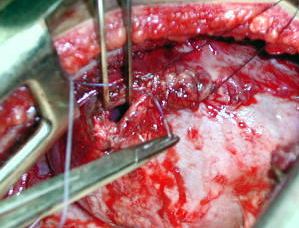

Toracotomía Izquierda

El contenido herniario intratoracico, toracotomía postero lateral Izquierda en 6To. espacio Intercostal:

• a - Epiplón mayor.

• b - Estómago.

• p - Pulmón.

• El contenido herniario liberado de las adherencias pulmonares y pleurales. El anillo herniario o agujero diafragmático, una vez incorporado al abdomen el contenido herniario y liberado de sus adherencias.

La frenorrafia se realizó con sutura de lenta reabsorción, calibre 1, de manera contínua, previa regularización de los bordes del anillo herniario y de la liberación de las adherencias, observe la liberación del diafragma, facilitando su movilidad, de importancia para la recuperación de la capacidad vital.